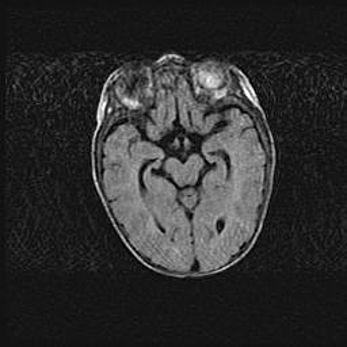

Церебральная ишемия II.

Возраст: 5 дней

Вес: 3400 г

Пол: женский

Окружность головы: 35 см

Срок гестации: 39 недель

Церебральная ишемия – это заболевание, характеризующееся недостаточностью (гипоксией) либо полным прекращением (аноксией) снабжения мозга кислородом по причине закупорки одного или нескольких сосудов. Это приводит к  что метаболическим расстройствам различной степени тяжести в тканях головного мозга, развитию коагуляционных некрозов и гибели нейронов.